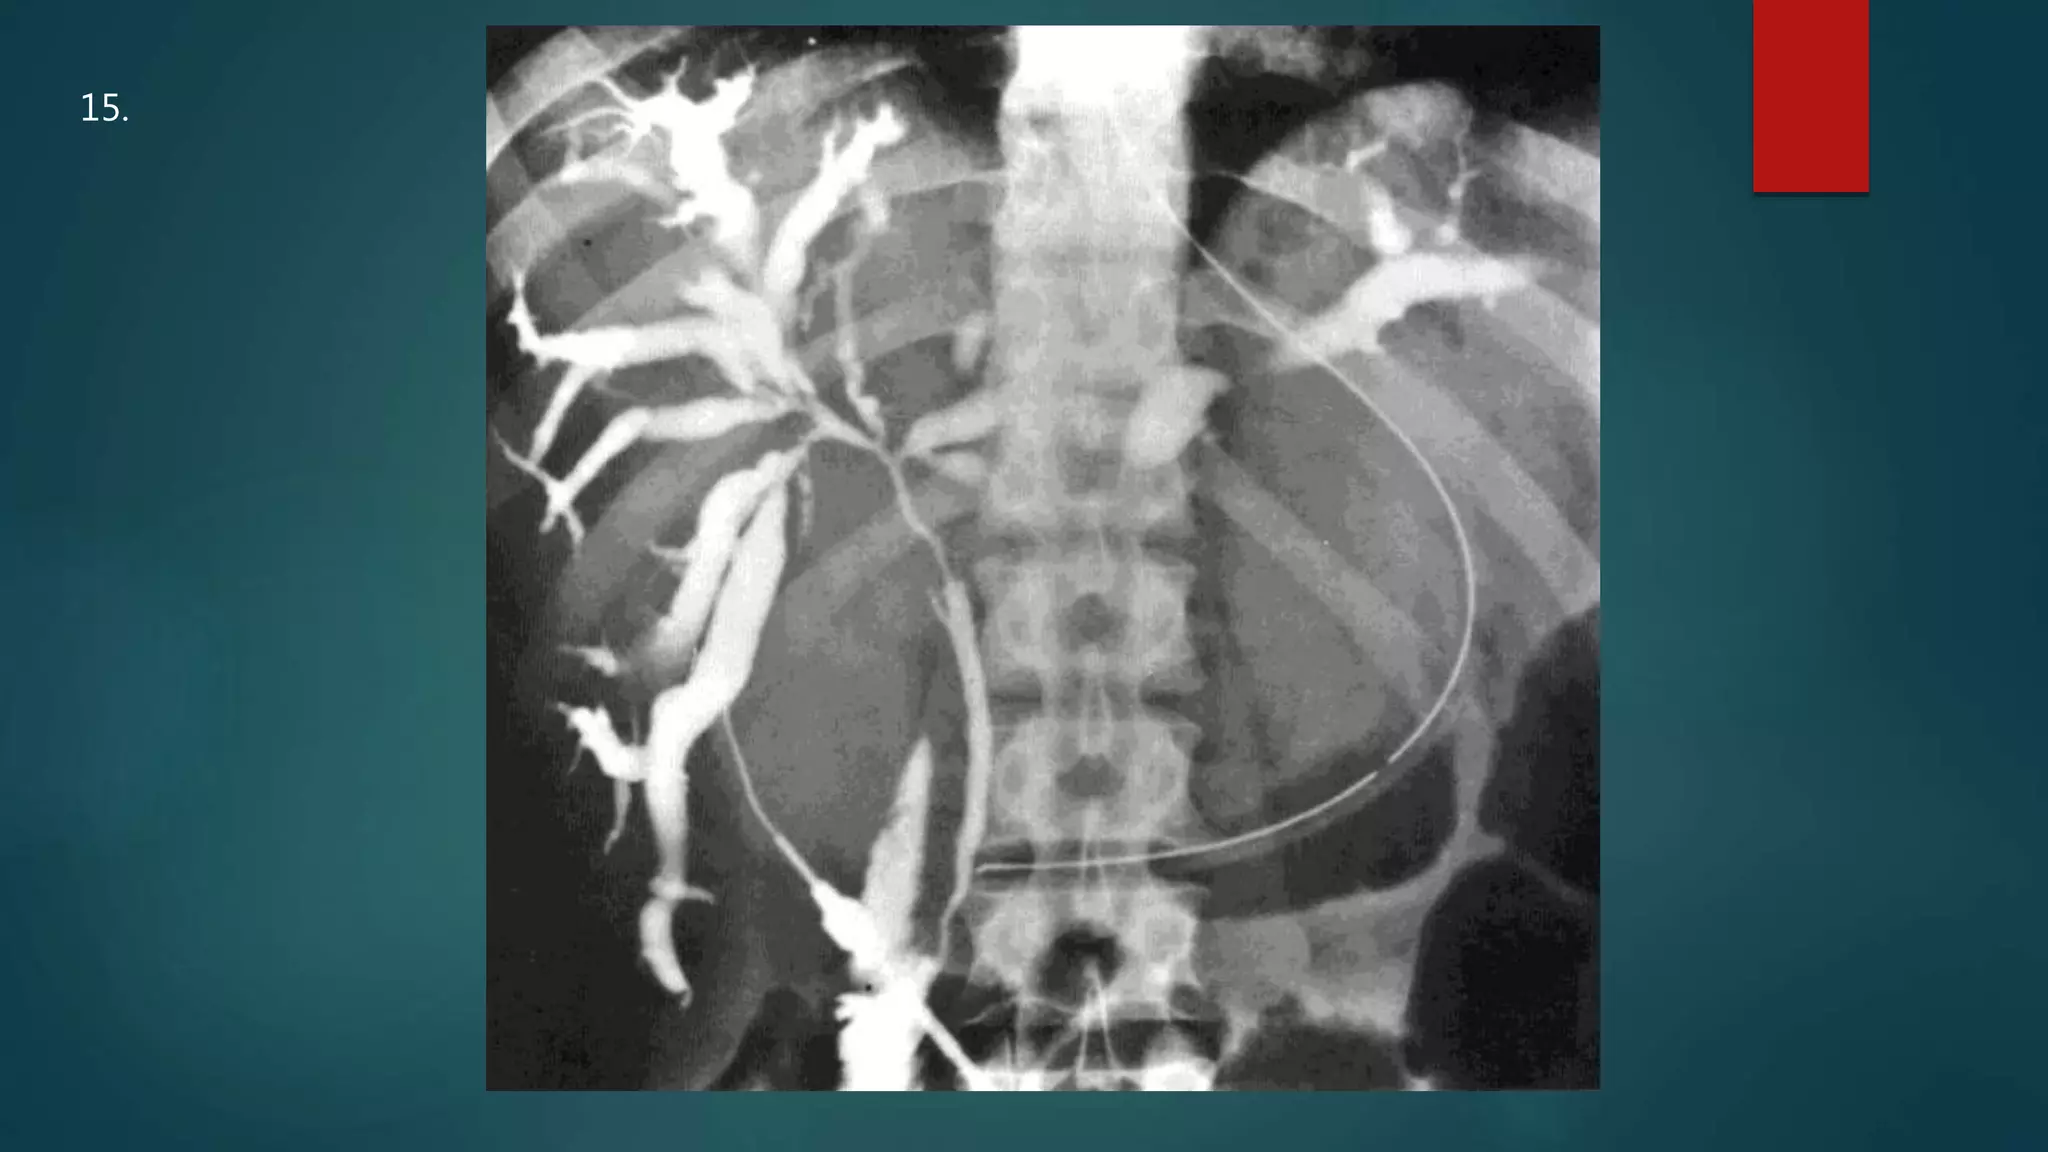

This document appears to be a medical report discussing several patients. It mentions a 35-year-old who was in a severe motor vehicle accident and an 81-year-old with a history of a non-vegetarian diet who had a perforated bowel from a chicken bone. The document provides few other details across its 25 numbered entries and was authored by Dr. Anish Choudhary for junior year 3 on May 30, 2016.